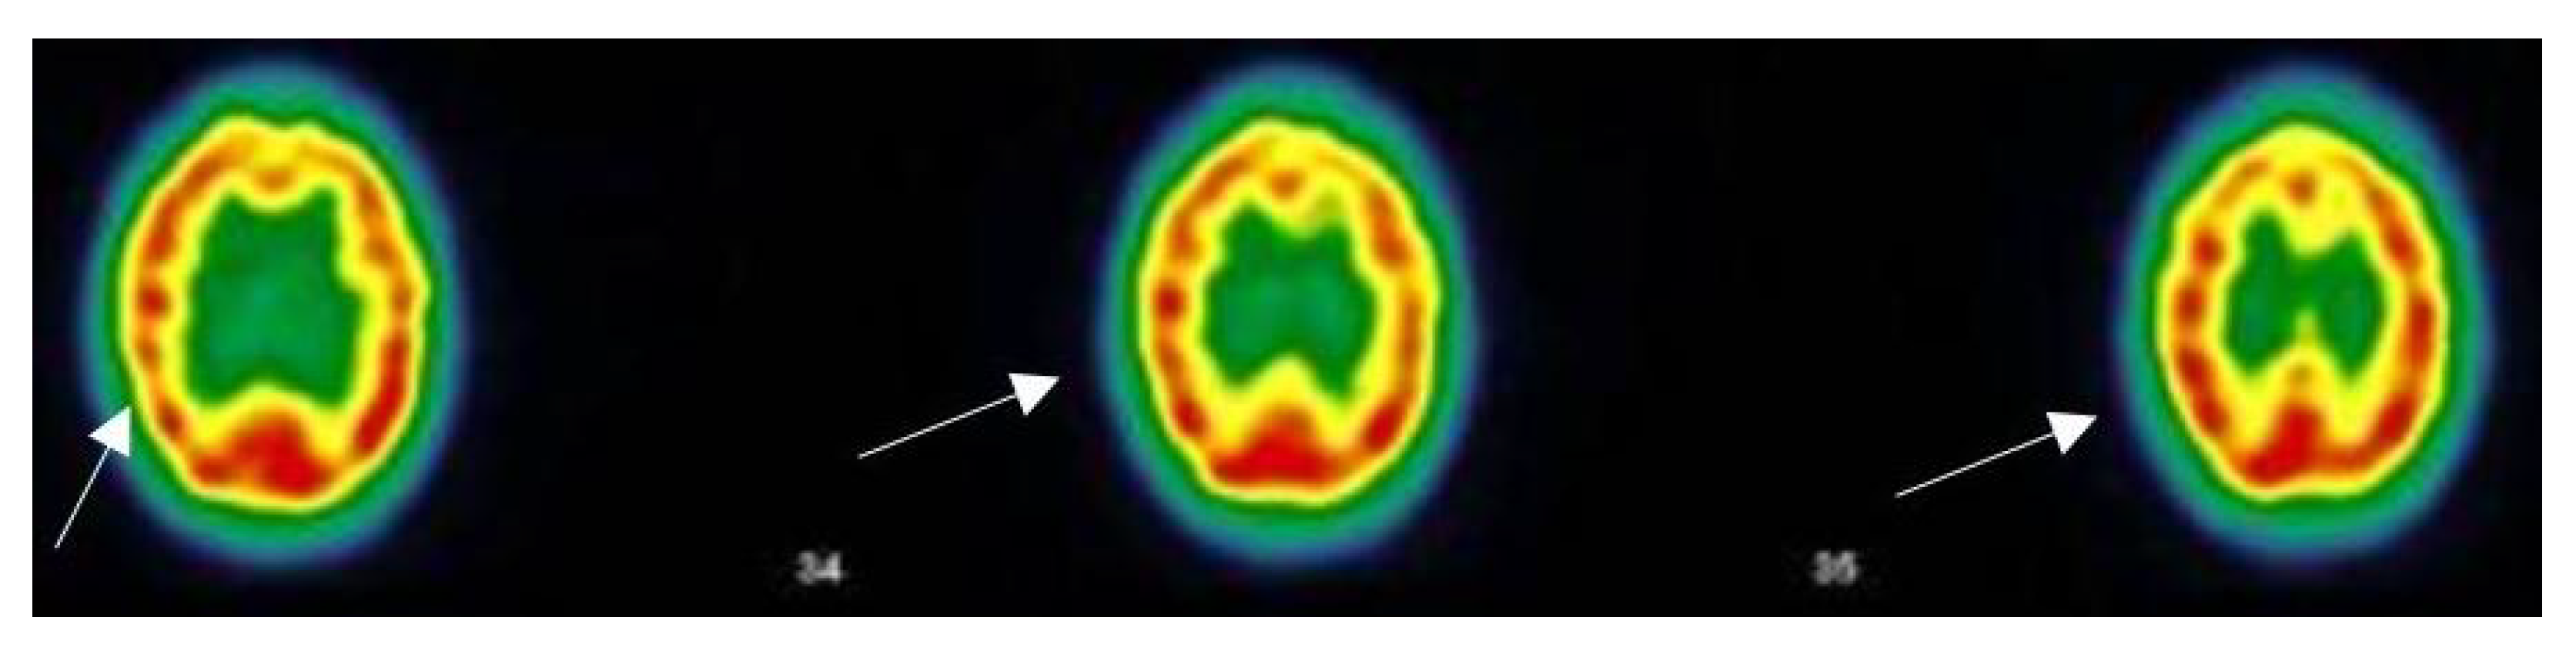

3.5. Narrative and SPECT-CT Images of Some Exemplary Cases

3.5.1. Patient MGA010

| 13 October 2020 Throat pain, rhinorrhea, bad aches, severe fatigue and headache, but no breathing difficulties, dysgeusia, anosmia. Stays at home, cured after 12 days. Home care only | 11 November 2020 Pain in both eyes, ocular pruritus, rapid ocular fatigue, noise intolerance, memory loss (forgets to pick up her daughter at school), concentration problems, remains isolated in her room, dyspnea at the slightest effort and at speech, almost continuous osteoarticular and muscular pains often with headaches, abnormal dreams, depressive feeling, fatigue, post-exertional malaise (PEM) | 27 July 2021 “On the images taken, left fronto-parietal, left frontal and left thalamic hypofixation is observed. No preservation of the sensory motor cortices. The fixation in front of the cerebellum is correct. Conclusion: Scintigraphic examination compatible with a cerebral pathology of the vascular type with clearer left fronto-parietal, left frontal and left thalamic vascular disorders”. |